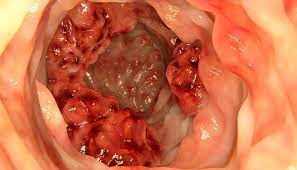

A Sociedade Brasileira de Coloproctologia (SBCP) realiza neste mês mais uma edição da campanha Maio Roxo, para alertar a população sobre as doenças inflamatórias intestinais (DIIs), que se caracterizam pela inflamação do trato gastrointestinal e podem atingir da boca ao ânus. Ao longo do mês, a SBCP divulgará textos e vídeos no Portal da Coloproctologia para esclarecer as principais dúvidas que envolvem as DIIs. A campanha destaca o Dia Mundial das Doenças Inflamatórias Intestinais, no próximo dia 19.

As doenças inflamatórias intestinais não têm cura. As mais comuns são a doença de Crohn e a retocolite ulcerativa. Adolescentes e jovens adultos são os mais afetados pelas DIIs. “São doenças crônicas em que se consegue um bom controle, mas o paciente não pode ficar sem o medicamento. O tratamento não é uma cura definitiva. O tratamento é para controle”.

Os principais sintomas são diarreias que duram mais de 15 dias, diarreias recorrentes com cólicas, sangue, muco ou pus nas fezes, perda de peso, urgência evacuatória, falta de apetite, cansaço. “São os sinais mais comuns das duas doenças inflamatórias intestinais. Acendem o alerta para que o paciente procure um especialista, que pode ser um médico gastroenterologista ou proctologista.”